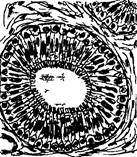

Между цитоподиями располагаются узкие щели, сообщающиеся с полостью капсулы. В эти узкие щели и собирается вначале первичная, фильтрующаяся моча из плазмы крови. Клетки наружного листка капсулы имеют вид плоских эпителиоцитов, лежащих на базальной мембране, они выстилают полость капсулы. Этот эпителий переходит в эпителий проксимальных канальцев (рис. 4). Эпителиоциты этого отдела нефрона имеют цилиндрическую форму. В этом канальце осуществляется обратное всасывание в кровь из первичной мочи ряда содержащихся в ней веществ. Поверхность клеток покрыта щеточной каемкой с высокой активностью щелочной фосфатазы, участвующей в полном обратном всасывании глюкозы. В цитоплазме клеток образуются пиноцитозные пузырьки, лизосомы. Базальная часть клетки характерно исчерчена, это внутренние складки цитолеммы и митохондрии между ними. Эпителий нисходящий части петли нефрона (петли Генле) плоский, ядросодержащие части клеток выбухают в просвет канальца. Цитоплазма клеток светлая. Восходящая часть петли Генле очень близка по строению с дистальным канальцем.

Рис. 4. Поперечный разрез канальцев нефрона

1 - извитой канадец 1-го порядка (проксимальный каналец); 2 - извитой каналец 2-го порядка (дистальный каналец); 3 - тонкая часть петли Генле; 4 - капилляр.